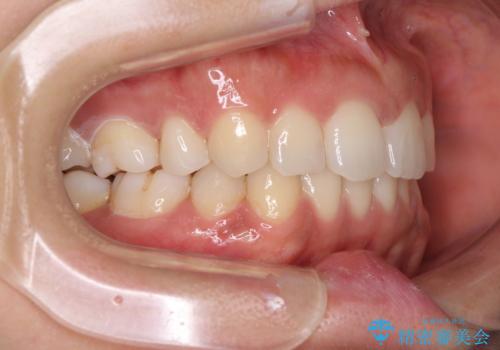

抜歯矯正の後戻り インビザラインによる再矯正治療

- 以前矯正治療をされていましたが、後戻りが起きたことを気にして来院された患者様です。

全顎的に認められた叢生を改善するため、インビザラインにて治療を行うこととしました。

前歯の叢生の改善を目的として、IPR(歯と歯の間を削る)と歯列全体の後方移動によって歯並びを整えることとしました。

毎日22時間の装着時間を守ってくださいましたが、ハイペースにマウスピースを交換することなく、慎重に治療を進めてくださったので、治療期間はやや長くなりました。

臼歯部も含め、叢生が綺麗に改善され、患者様には大変満足していただきました。